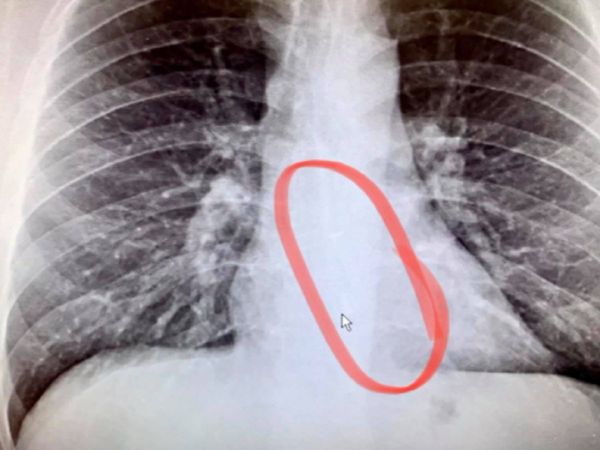

अमेरिका में ब्रैडफोर्ड गौथियर नाम का एक शख्स सोते समय अनजाने में एयरपॉड को निगल गया। सुबह उठकर उसे पानी पीने में दिक्कत हुई। डॉक्टरों ने जब एक्स रे किया तो सच्चाई सामने आई, इसके बाद उसे निकाला गया।

उनकी पत्नी उन्हें तुरंत अस्पताल में लेकर गई, जहां डॉक्टरों ने एक्स-रे किया। इससे पता चला कि ईयरफोन शरीर में अंदर फंसा हुआ है। इस निकालने के लिए इमरजेंसी एंडोस्कोपी की गई। वो लोगों को आगे चेताते हुए कहते हैं कि जब आप सोने जाते हैं तो वायरलेस हेडफोन से सावधान रहें, आपको कभी नहीं पता चलेगा कि किस मुश्किल में फंस सकते हैं।